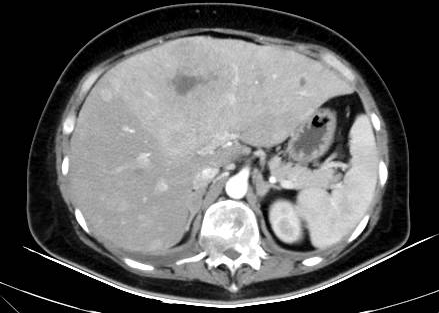

超声(2023-5基线):左乳11点见低回声占位,约3.1cm×2.6cm,边界不清、形态不规则,内见丰富血流信号,BI-RADS 6类;右乳片状低回声区,建议密切观察。双锁骨上区见低回声占位(左侧约1.8cm×1.5cm,右侧约2.4cm×1.1cm),左腋下见2.1cm×0.9cm低回声淋巴结,均考虑转移。肝体积增大、回声欠均匀,内见多发稍高回声占位(部分内见无回声区),较大约7.3cm×5.1cm,边界不清,考虑转移。

腹部CT(2023-5基线):肝脏体积增大,实质内弥漫多发稍低密度结节/肿物(部分可疑融合),较大约121mm×96mm,内见低密度坏死区;增强扫描动脉期高强化,门脉期强化稍减低,考虑转移。肝右后叶下方见11mm×10mm软组织密度结节,脾内见36mm×30mm稍低强化肿物(边界均不清),均考虑转移。双侧肾上腺不均匀增粗,伴15mm×8mm低强化结节,转移可能大。右肾微小囊肿。胆囊、胰腺、左肾未见异常。膀胱部分充盈,壁无明显增厚。左侧附件区形态饱满、强化欠均匀,转移待除外;子宫及右侧附件区未见异常。肝门区及腹膜后见26mm×17mm肿大淋巴结,考虑转移。腹腔、双侧髂血管旁及腹股沟区无肿大淋巴结,无腹盆积液。

治疗仅8周后,复查胸CT、腹盆CT、头MR、肿瘤标志物,评效结果为缩小的SD,肿瘤标志物下降,肝功能恢复正常。基线27mm的肺部病灶在持续治疗中不断缩小,至2025年4月CT复查完全消失,并维持至今。脑转移灶5mm缩小至2-3mm。